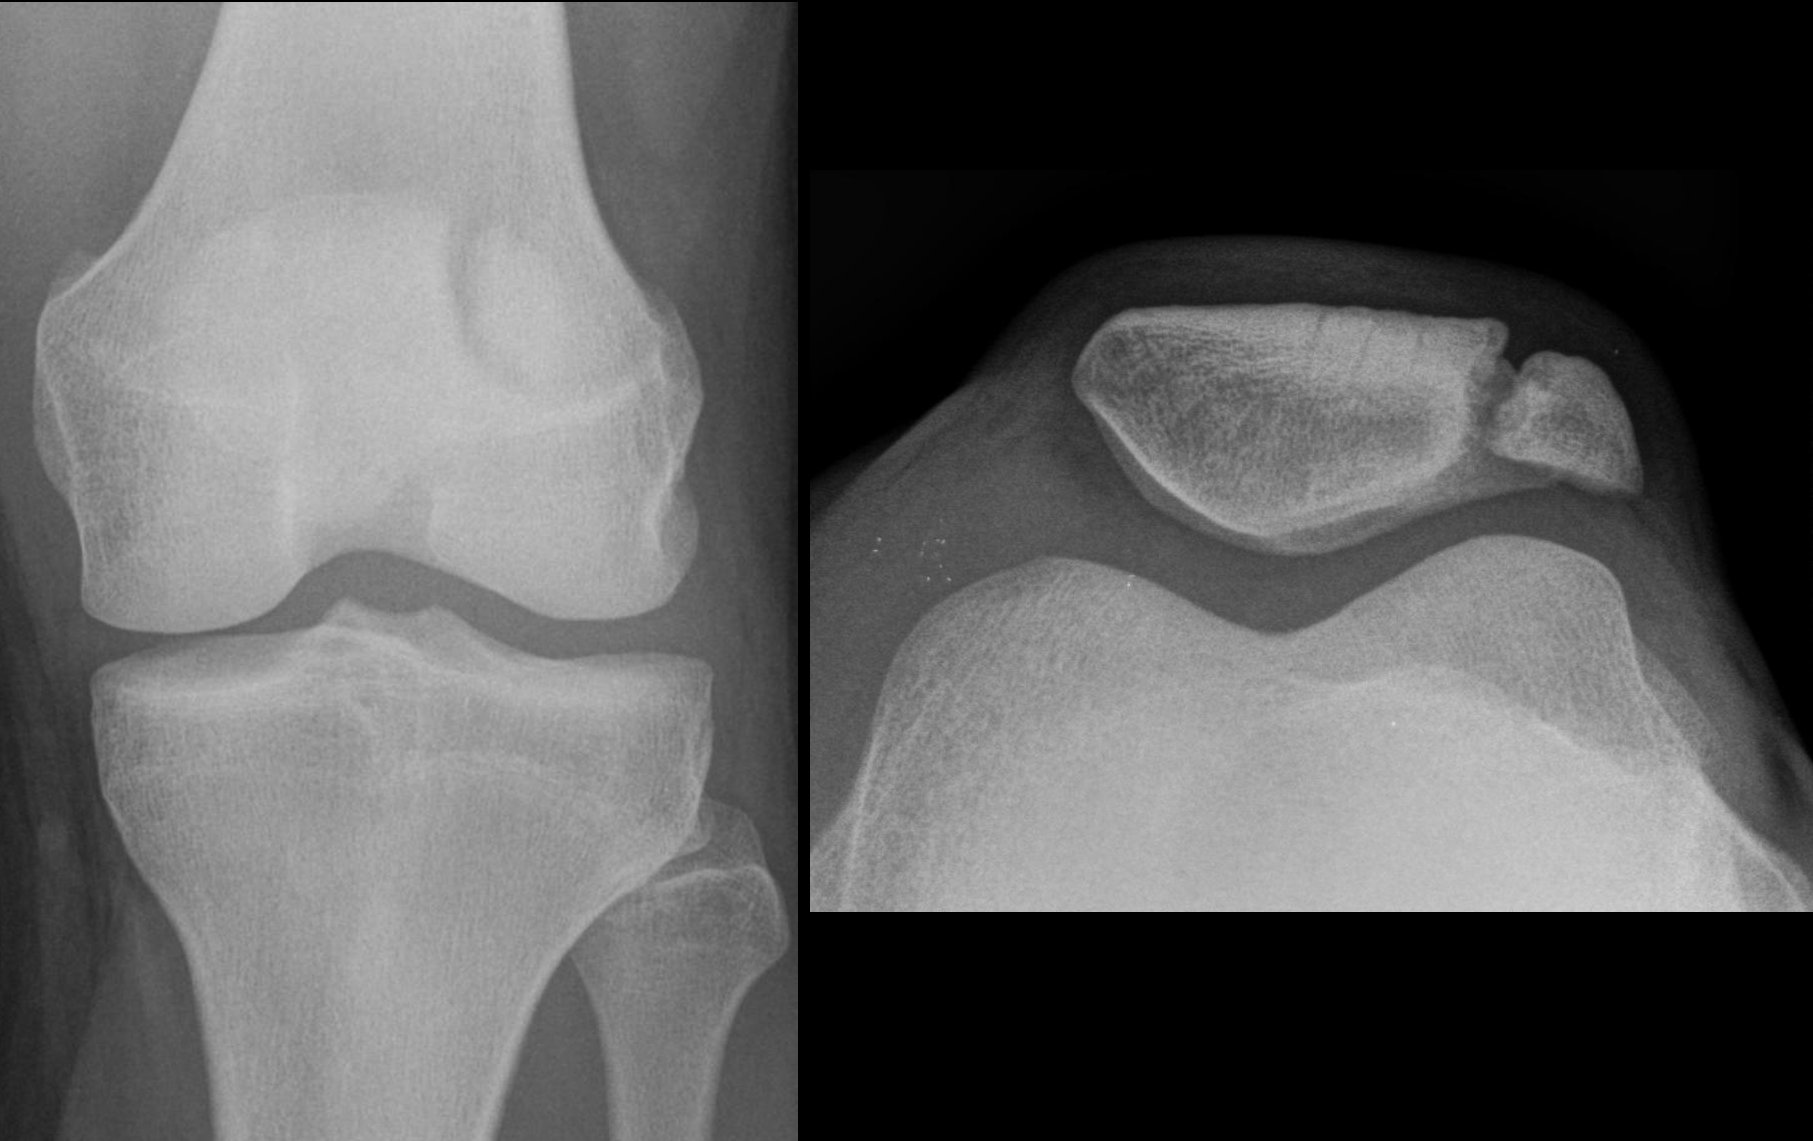

슬개골 탈구는 특히 젊은 여성 운동선수에게서 상당한 빈도로 발생한다.[2] 이는 무릎의 슬개골이 제 위치에서 벗어나는 것을 포함하며, 대부분 바깥쪽으로 탈구되고 극심한 통증과 부종을 동반할 수 있다.[3] 슬개골은 무릎을 펴는 동작으로 다시 홈으로 되돌아갈 수 있으며, 때로는 저절로 제 위치로 돌아가기도 한다.[3]4. 2. 무릎뼈 골절 (Patellar fracture)

무릎뼈는 특히 노출된 위치 때문에 부상을 입기 쉽고, 무릎뼈 골절은 일반적으로 무릎에 직접적인 외상으로 인해 발생한다. 이러한 골절은 대개 해당 부위의 부기, 통증, 관절 내 출혈(혈관절증), 무릎을 펼 수 없는 증상을 유발한다. 무릎뼈 골절은 손상이 경미하고 신전(伸展) 기전이 온전한 경우를 제외하고는 대개 수술로 치료한다.[7]4. 3. 무릎뼈 위치 이상